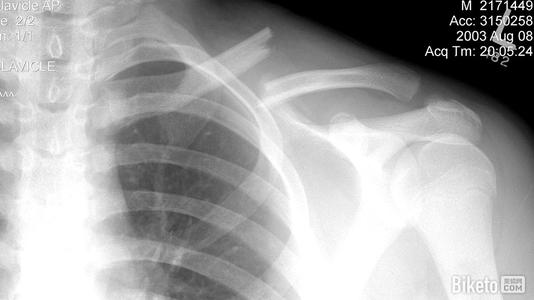

本病的辅助检查方法主要是影像学检查,锁骨骨折常发生在中段。多为横断或斜行骨折,内侧断端因受胸锁乳突肌的牵拉常向上后移位,外侧端受上肢的重力作用向内、下移位,形成凸面向上的成角、错位缩短畸形。

1.X线检查

疑有锁骨骨折时需摄X线像确定诊断。一般中1/3锁骨骨折拍摄前后位及向头倾斜45°斜位像。拍摄范围应包括锁骨全长,肱骨上1/3、肩胛带及上肺野,必要时需另拍摄胸片。前后位像可显示锁骨骨折的上下移位,45°斜位像可观察骨折的前后移位。

内侧断端因受胸锁乳突肌的牵拉常向上后移位,外侧端受上肢的重力作用向内、下移位,形成凸面向上的成角

外1/3锁骨骨折中,一般可由前后位及向头倾斜40°位X线像做出诊断。锁骨外端关节面骨折,常规X线像有时难以做出诊断,常需摄断层X线像或行CT检查。